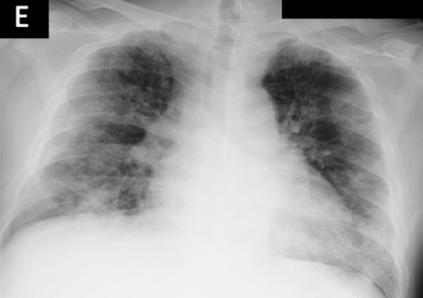

Across the world's coronavirus disease 2019 (COVID-19) hot spots, the need to streamline patient diagnosis and management has become more pressing than ever. As one of the main imaging tools, chest X-rays (CXRs) are common, fast, non-invasive, relatively cheap, and potentially bedside to monitor the progression of the disease. This paper describes the first public COVID-19 image data collection as well as a preliminary exploration of possible use cases for the data. This dataset currently contains hundreds of frontal view X-rays and is the largest public resource for COVID-19 image and prognostic data, making it a necessary resource to develop and evaluate tools to aid in the treatment of COVID-19. It was manually aggregated from publication figures as well as various web based repositories into a machine learning (ML) friendly format with accompanying dataloader code. We collected frontal and lateral view imagery and metadata such as the time since first symptoms, intensive care unit (ICU) status, survival status, intubation status, or hospital location. We present multiple possible use cases for the data such as predicting the need for the ICU, predicting patient survival, and understanding a patient's trajectory during treatment. Data can be accessed here: https://github.com/ieee8023/covid-chestxray-dataset